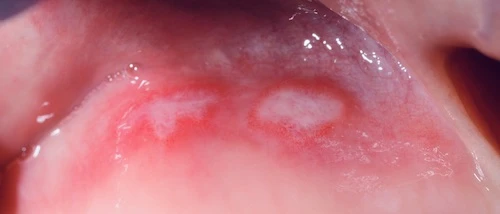

Canker sore, also known as aphthous stomatitis, is an ulceration of the mucous membrane in the oral cavity, characterized by a yellowish or whitish color surrounded by an inflamed area.

They develop on the cheek, the palate, or the tongue, ranging from small to large circular or oval shapes, occasionally less regular in shape initially, appearing as yellowish, then grayish-white ulcers. The ulcers on the mucous membrane are surrounded by a red, inflamed area. They can appear individually or in small clusters.

The size of canker sores varies considerably (1-30mm), but they are most commonly the size of a peppercorn.

Minor aphthous stomatitis (MiRAS), also known as Mikulicz ulcer, is the most common type (affecting 80% of RAS sufferers). They are typically smaller than 5 mm in size, occurring singly or in clusters, and are oval or round in shape. They usually affect the movable, non-keratinized mucosa.

They heal within 7-10 days without scarring. The ulcers are shallow in depth. Recurrence is very common, but the duration of ulcer-free periods varies from person to person. They typically involve mild pain.